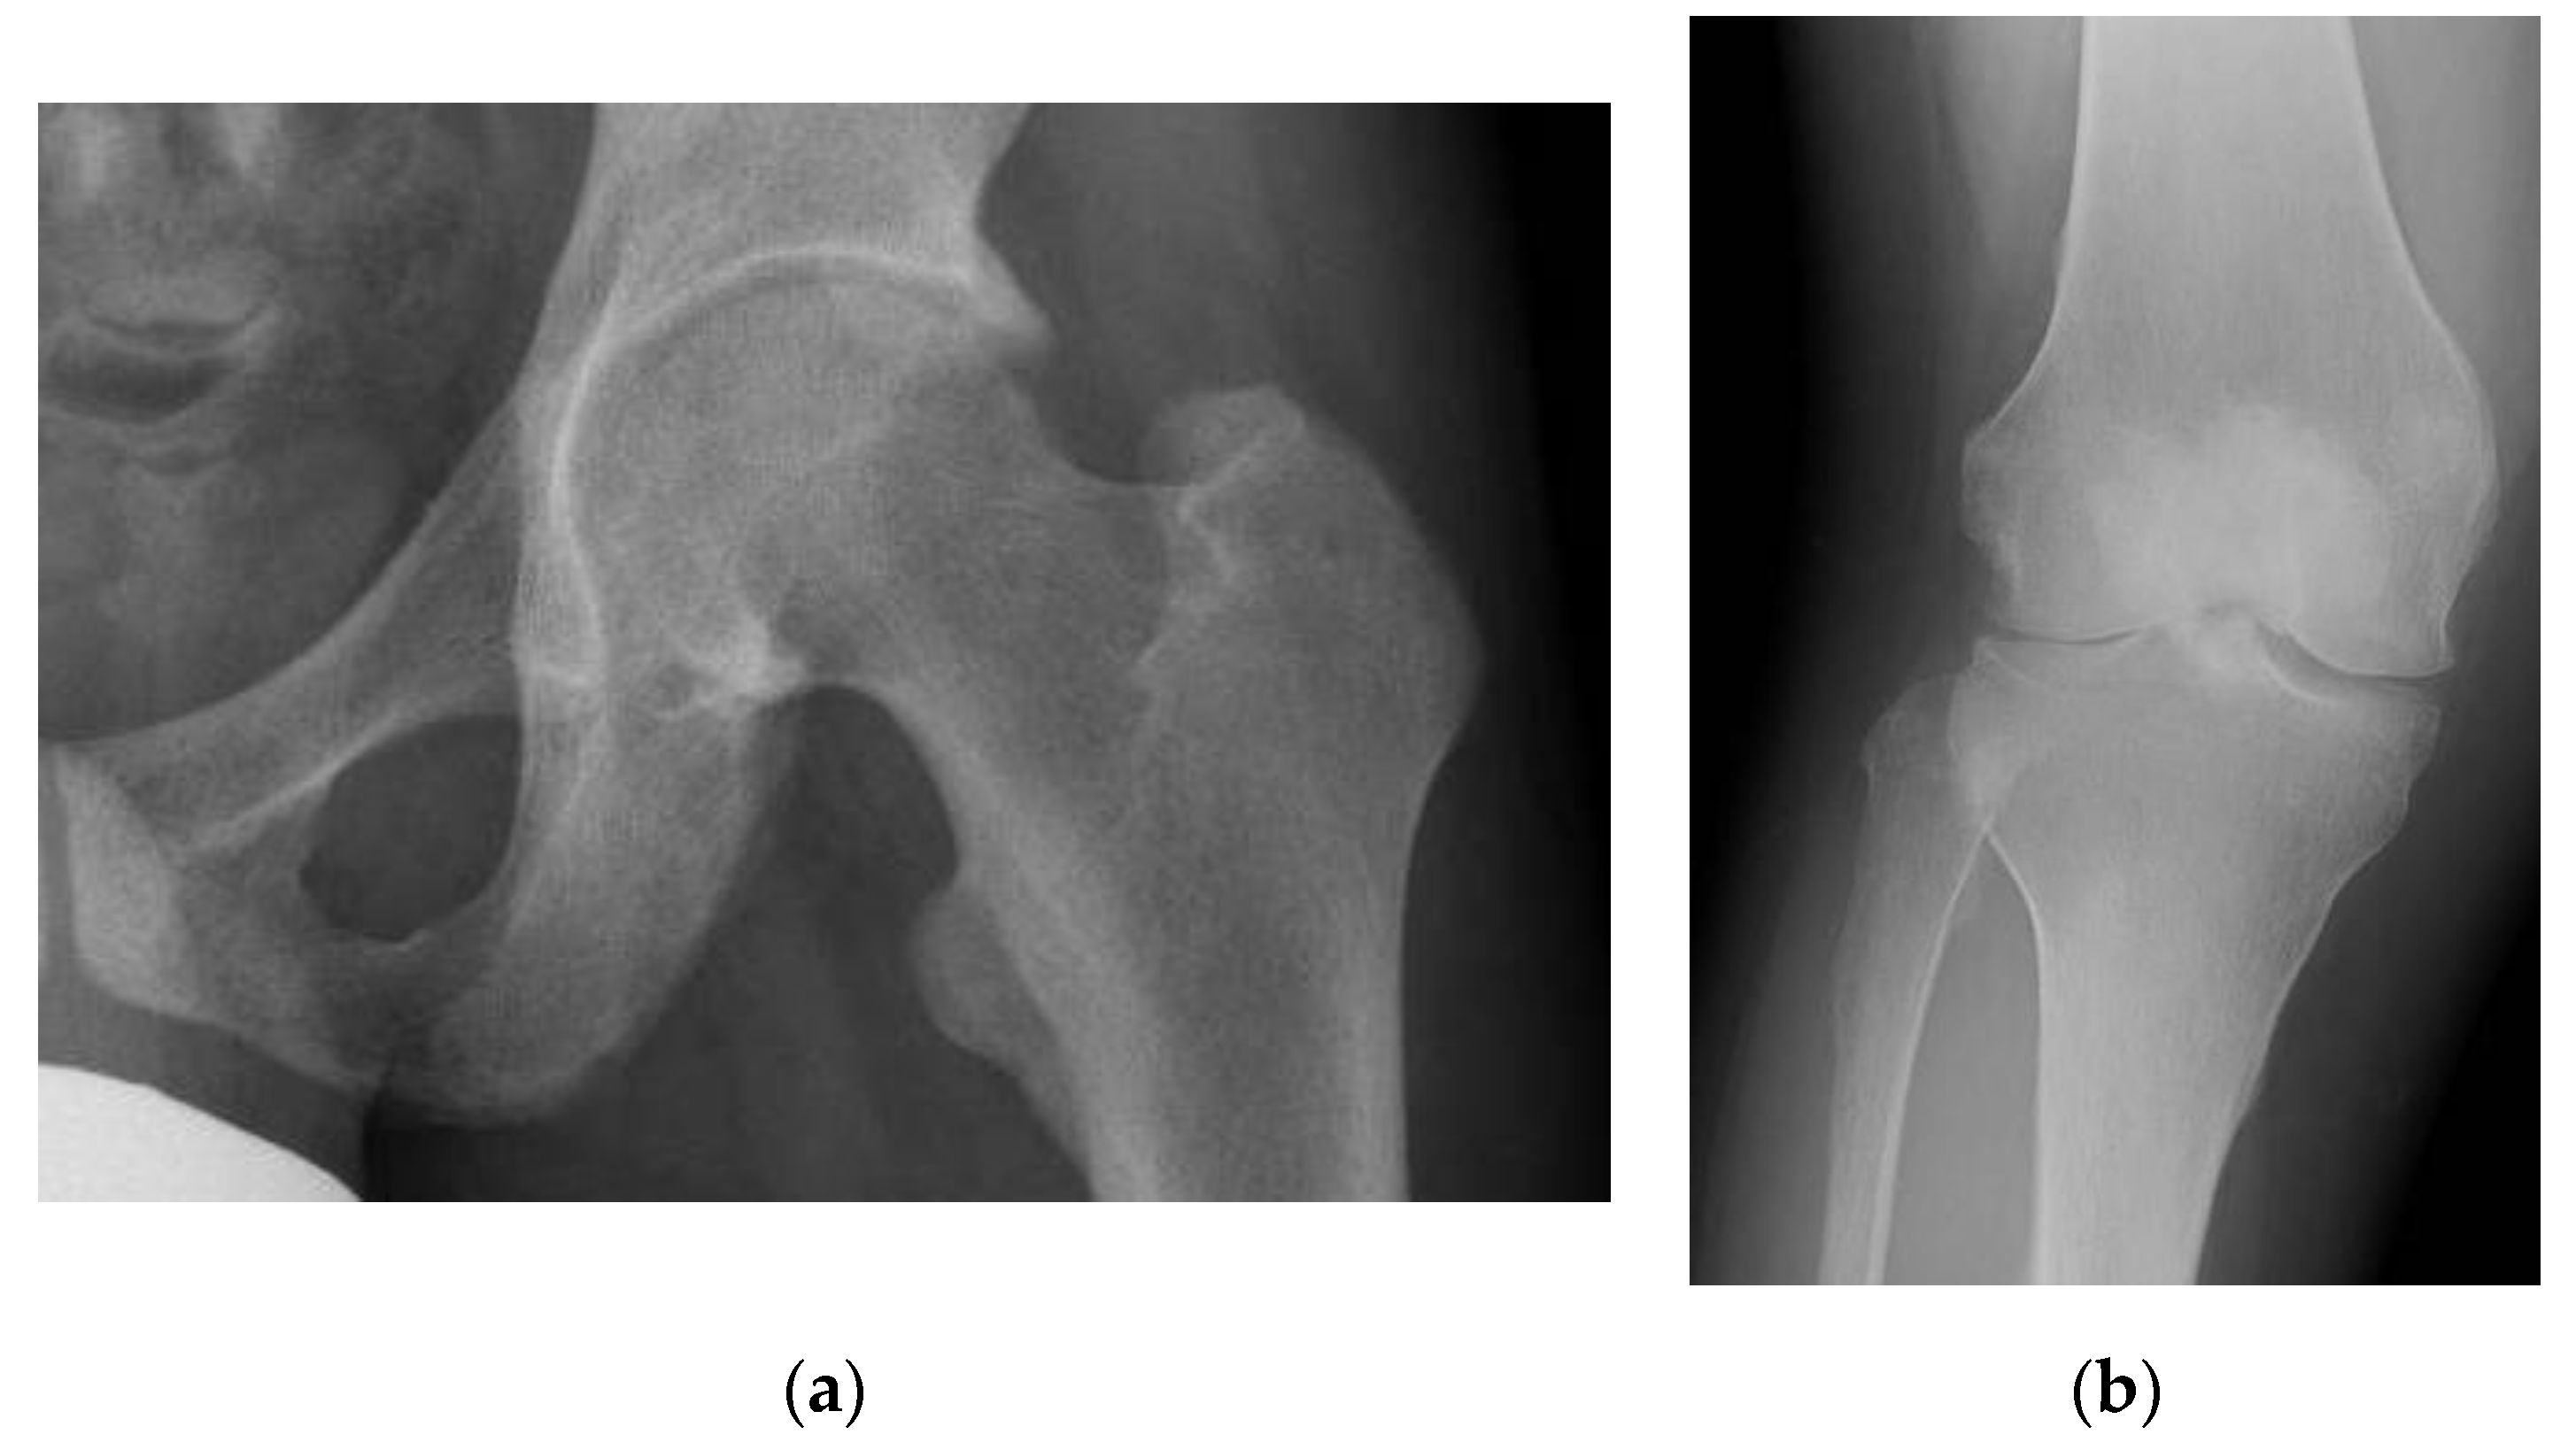

3.1. Pseudofracture and Fracture

3.4. Enthesopathy

3.5. Osteoarthritis